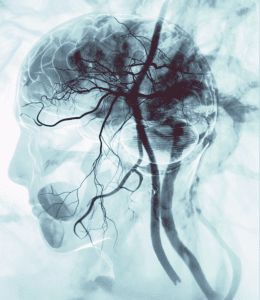

cerebral angiogram